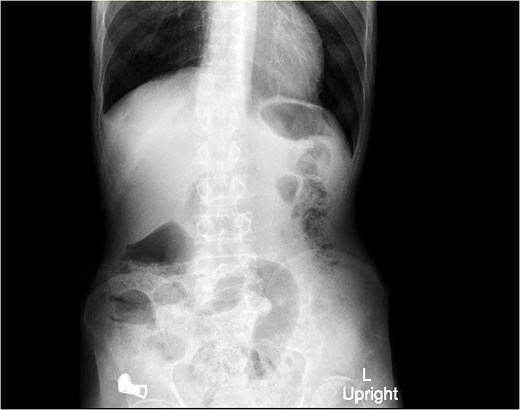

X-ray abdomen (erect) (Fig. 2): Non-specific bowel gas distribution; no free air or masses identified.

X-ray abdomen (erect) showing non-specific bowel gas distribution; no free air or masses identified.